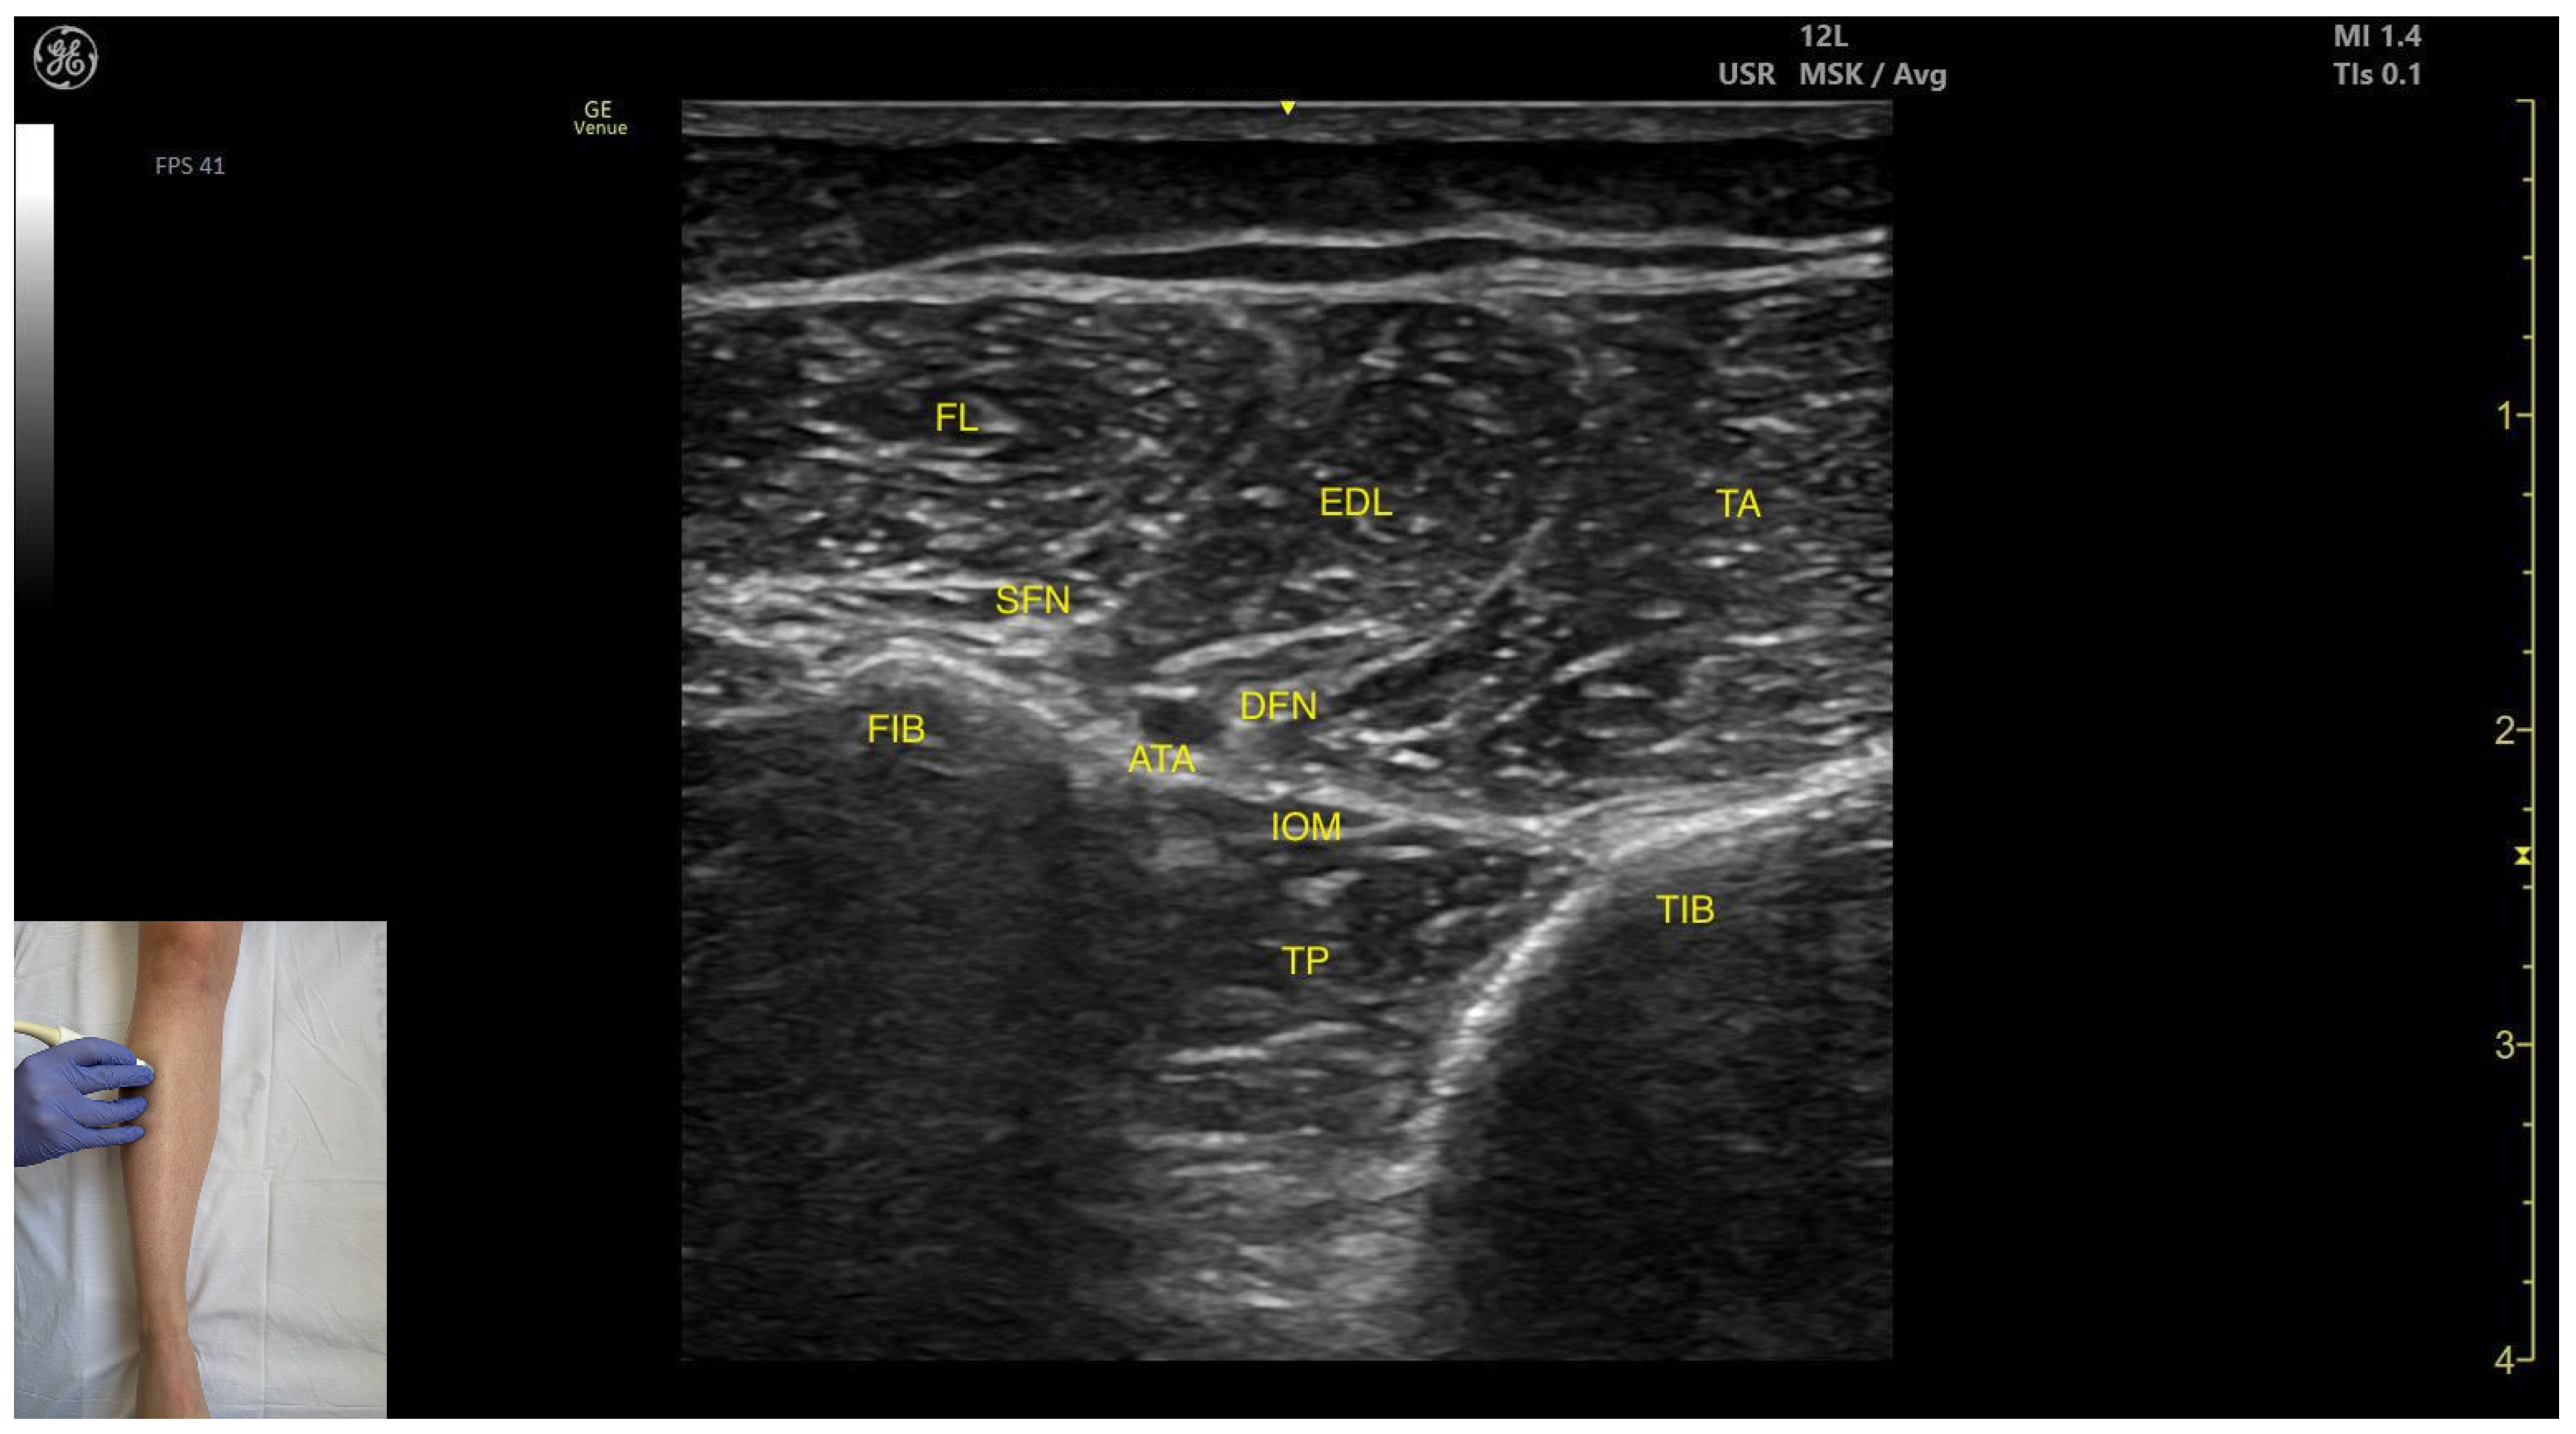

3.10.2. Ultrasound Identification

3.10.3. Key Ultrasound Landmarks

- Muscle position: It occupies the most posterior and lateral position within the anterior compartment of the leg. It lies superficially beneath the subcutaneous plane. Medial to it lies the tibialis anterior; lateral to it lies the fibularis longus.

- Neurovascular bundle: The superficial fibular nerve courses within the intermuscular fascia between the EDL and fibularis longus. Deep structures include the interosseous membrane, tibialis posterior muscle, deep fibular nerve, and the anterior tibial artery.

- External fascia: It presents a pronounced fascia that demarcates it from the superficial plane and adjacent muscles (tibialis anterior and tibialis posterior), aiding in safe BoNT-A injection.

- Dynamic evaluation: During dynamic evaluation, scanning toward the ankle joint, the EDL muscle thickness decreases as the EHL appears deep to it. Muscle contraction is visible during toe extension of digits II–V and dorsiflexion at the ankle joint.

| Extensor Digitorum Longus | Proximal third of the anterior aspect of the leg, in the lateral portion | Tibialis anterior (medial); Fibularis longus (lateral); superficial fibular nerve, anterior tibial artery, deep fibular nerve (deep) | Transverse scan on proximal third of the anterior aspect of the leg | Visualize extensor digitorum longus as most superficial muscle and confirm muscle position and relations |